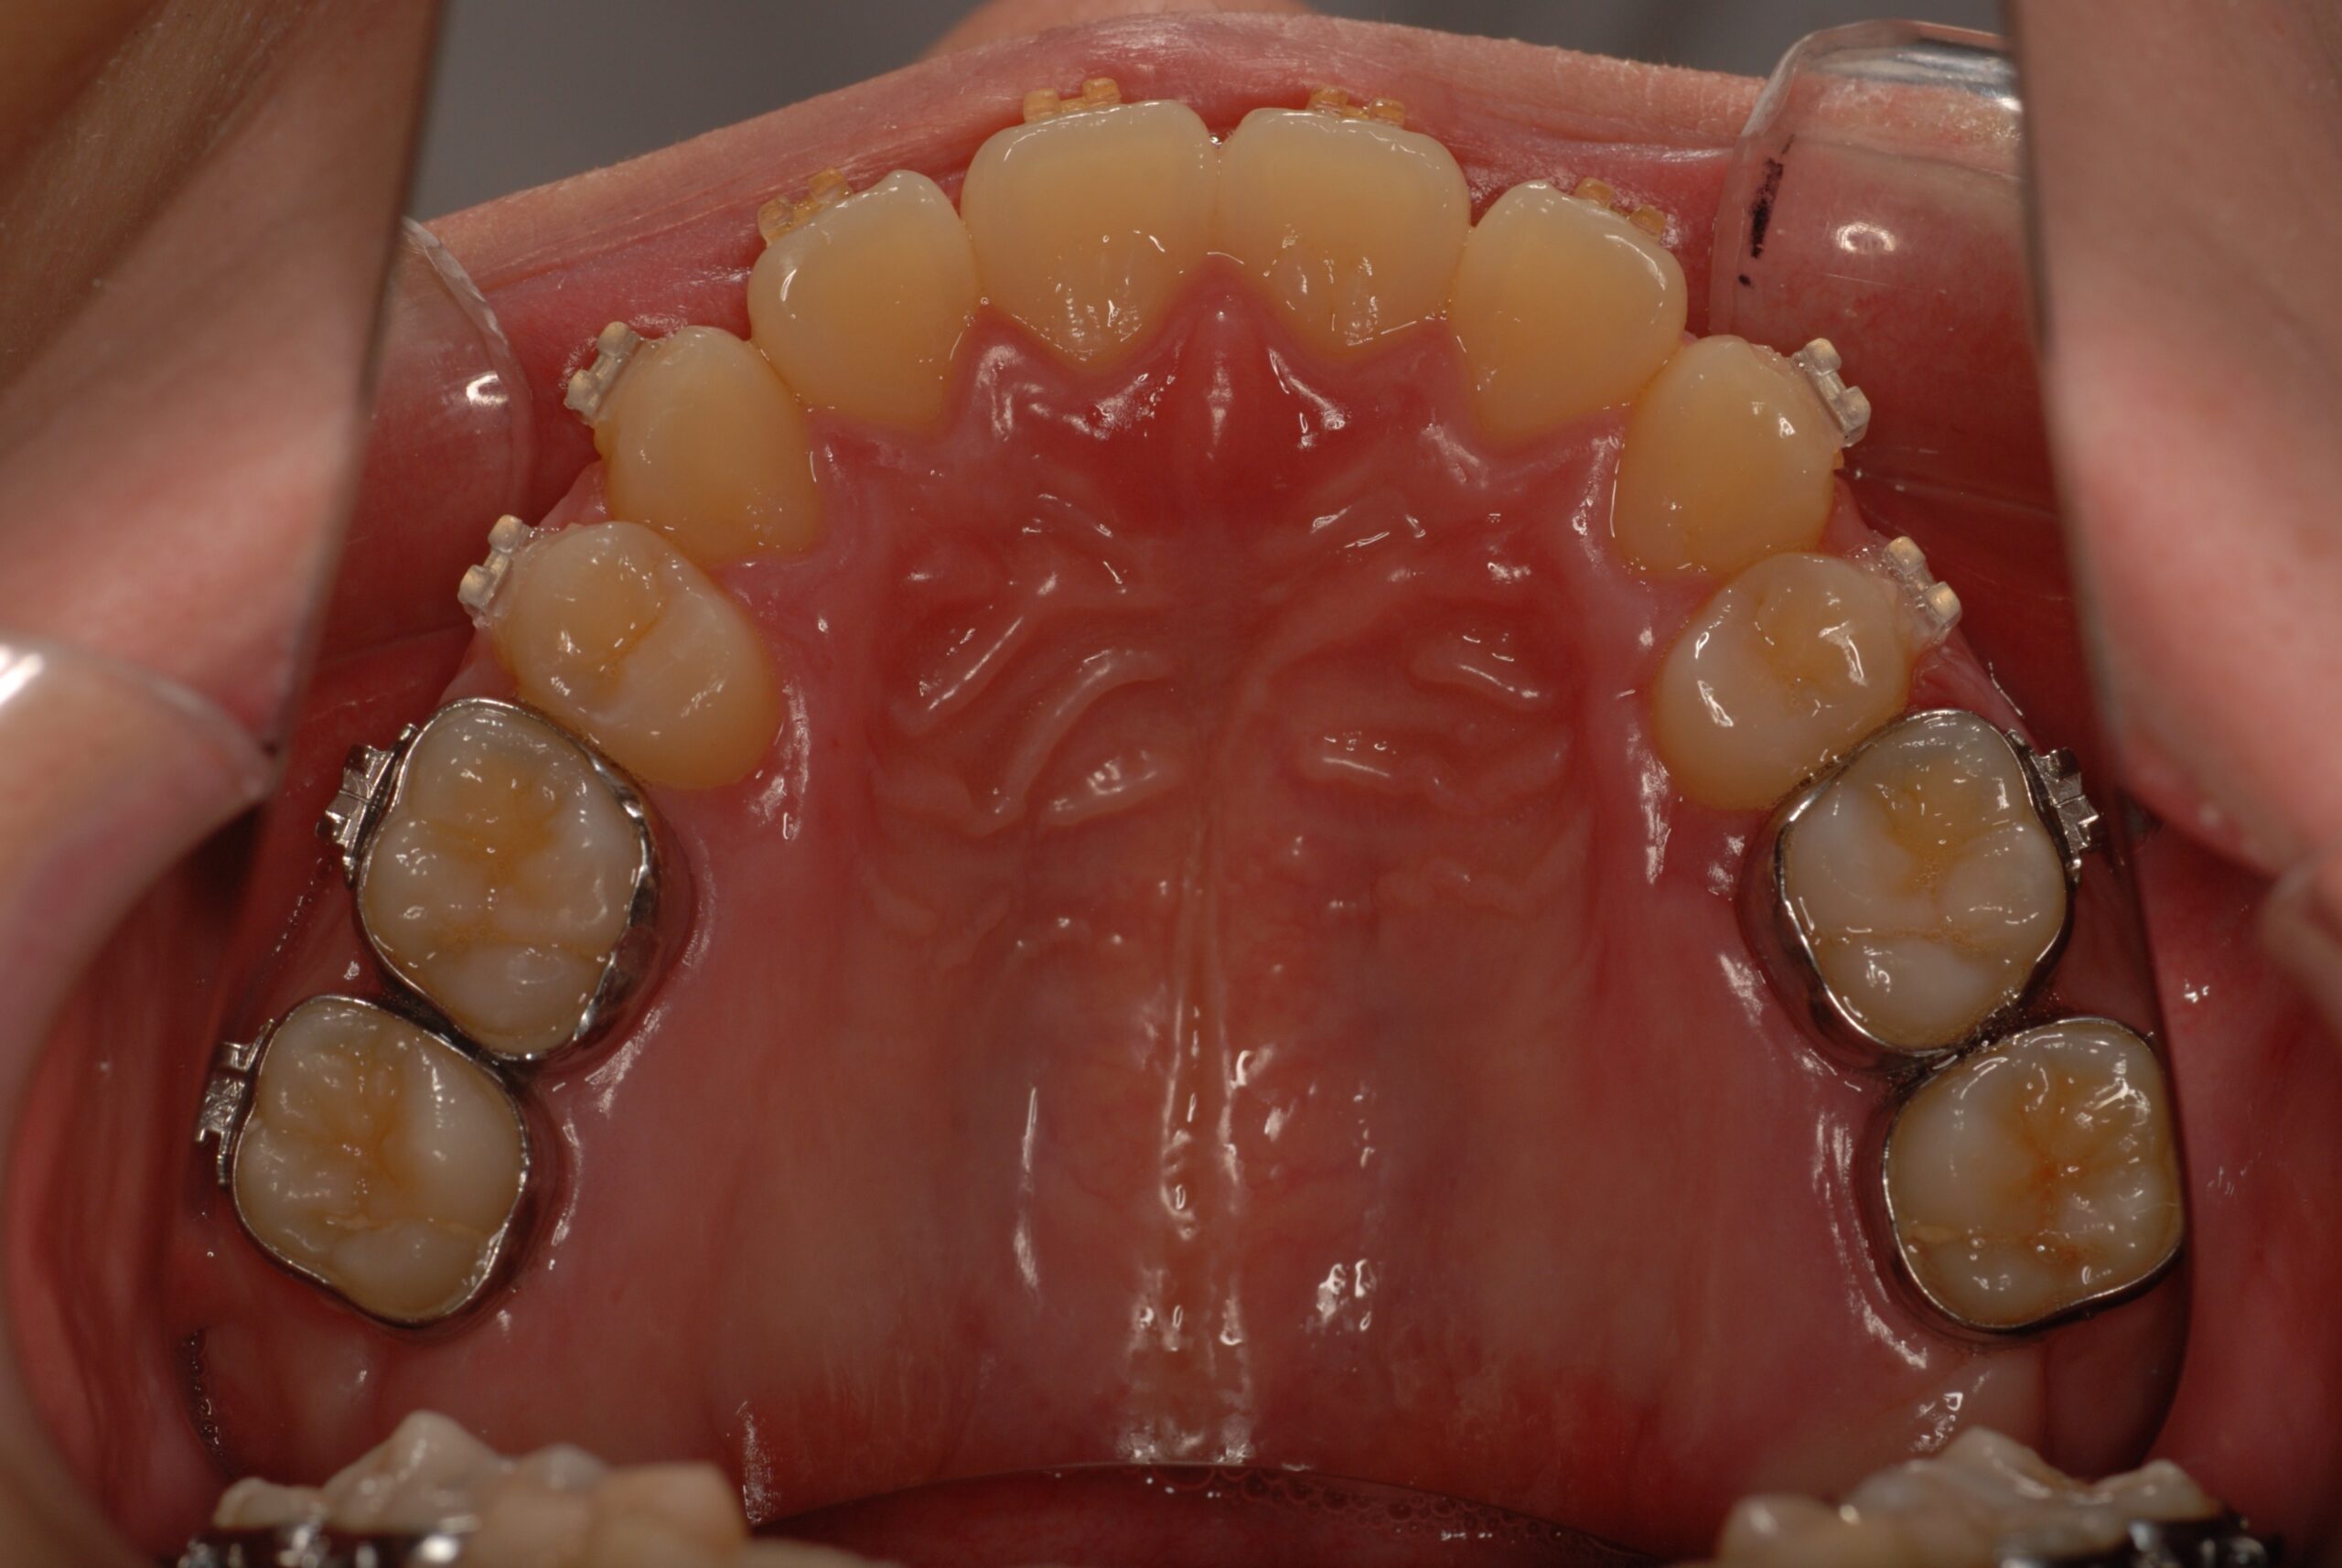

反対咬合(受け口、下顎前突) 叢生

- 骨格性下顎前突症、下顎骨左偏位、叢生、 顎変形症として、外科的矯正術を計画。 叢生、右側第2大臼歯鋏状咬合。 上下顎第一小臼歯を抜歯し、抜歯空隙を利用し叢生を改善し、上下顎それぞれ歯列を整列し、矯正治療中に病院歯科口腔外科にて外科手術(近郊の病院歯科口腔外科にて、口の中から手術、2週間入院)により下顎骨の後退と左偏位の改善をし、適切なオーバージェット、オーバーバイトを付与する。